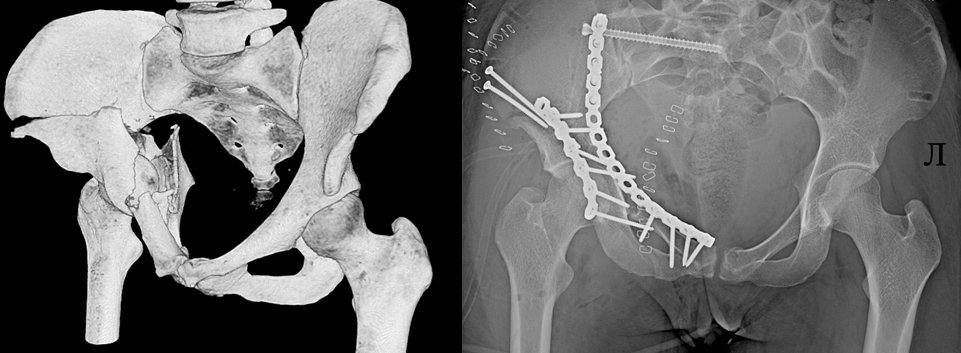

В новогодние каникулы в «соловьёвку» привезли пятерых пострадавших на горках. Наиболее тяжёлые травмы получила 25-летняя девушка. Она, спускаясь с горки на «ватрушке», на скорости врезалась в бетонный блок. Пострадавшую экстренно доставили в больницу, где врачи диагностировали множественные переломы костей таза. Пациентку даже пришлось направить в реанимацию, а после стабилизации состояния — на пятичасовую операцию. Врачи установили сломанные кости в правильном положении и зафиксировали металлоконструкциями. Теперь пациентку ждёт длительная реабилитация.

Фото: ГАУЗ ЯО «Клиническая больница им. Н. В. Соловьёва»